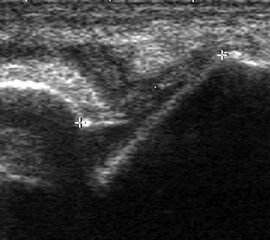

Ruptur Lig. fibulocalcaneare

Längsschnitt über dem Lig. fibulocalcaneare. Die Peronealsehnen erscheinen als echoreiche runde bis ovaläre Struktur.

Abbildung 19

Lagerung: Rückenlage, OSG in Neutralstellung.

Schnittebene: LS über Lig. fibulocalcaneare.

Referenzstrukturen: Fibulaspitze und Talus.

Befunde: Das Lig. fibulocalcaneare is nativ schlecht abgrenzbar, da es in die Tiefe und nicht parallel zum Schallkopf verläuft. Direkt über das Band ziehen quer getroffen die Peronäussehnen. Durch die Distorsion kann auch das Peritendineum peroneale einreißen. Die Peronealsehnen sind dann in ihrer Sehnenscheide von Blut umgeben, was sich als echoarmer Ring (Halo-Phänomen) darstellt und ein indirektes Zeichen für eine Verletzung des Lig. fibulocalcaneare ist.